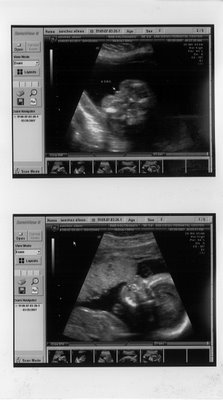

We're having a...

GIRL!